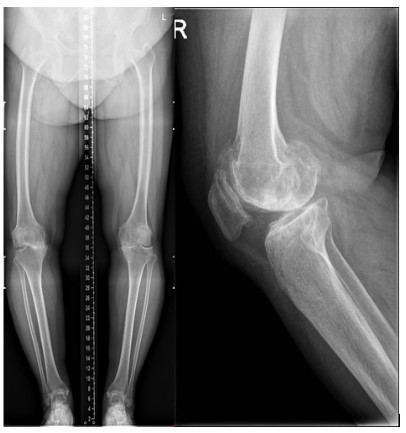

A female, aged 55, with 153 cm in height, 85 kg in weight and 36.3 in BMI. She was admitted to hospital on July 24, 2021 due to severe osteoarthritis of the right knee. Physical examination manifested severe varus deformity of affected limb with limited flexion and extension activities, with ROM: 80°-10°-0° (Figure 1). The patient received TKR on July 27, 2021. She was permitted walking one day post-operatively, and was discharged one week later (Figure 2).

Figure 2: Case 1 after knee replacement

Case 2 was also a female with 58 in age, 160 cm in height, 65 kg in weight and 25.4 in BMI. She was admitted to hospital on December 08, 2020 due to severe osteoarthritis of the left knee. Physical examination manifested severe deformity of the affect limb with limited flexion and extension activities, with ROM: 100°-10°-0° (Figure 5).

TKR was implemented for her left knee under general anesthesia on December 08, 2020. And 1 day later after surgery, she began to walk with crutches (Figure 6). The patient was discharged 1 week post-operatively with satisfactory recovery.

Figure 5: Case 2 prior to admission

Figure 6: Case 2 after knee replacement

As for the reasons, we deduced that post-operative changes in biomechanical axis of knee joint, increasing activity levels, osteoporosis and BMI mass index played great role in leading to stress fracture of femoral neck. Furthermore, the bilateral varus deformity of the knee joint was severe in these two patients, lower limb load axis after TKR is significant changed (Figures 1,2,5,6), resulting in concentrated creation on the femoral neck cortex. When full weight bearing, activity levels increased and excessive loading of the hip may cause the tendency of hip varus, bring about the possibility of fracture. Those two patients (Tables 1,2), Osteoporosis index 25 hydroxyvitamin D was lower than normal, they are osteoporosis, Bone density and mass decrease, and bone microstructure is destroyed, resulting in increased bone fragility, which can lead to fractures. The BMI of case 1 is 36.3, severe obesity, excessive loading of the right hip, so we assume that changes in biomechanical axis of knee joint after TKR, activity levels increased, osteoporosis and BMI mass index can lead this infrequent complication.